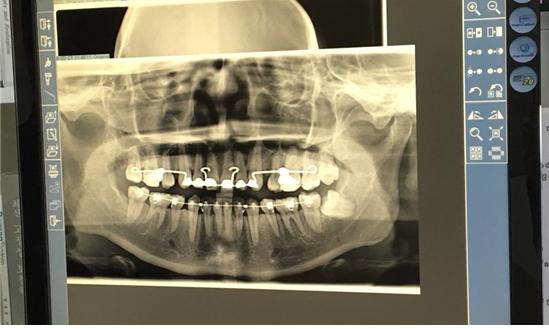

<엑스레이 사진으로 돌출입교정전후 변화를 비교해주셨어요>

상악장치를 뺄지 정하기 전에 엑스레이 사진으로 지금 상태를 확인해주셨는데요,

와 일년만에 저렇게 돌출입교정전후 변화가 ㅋㅋㅋㅋㅋ

잇몸뼈 들어간거 보이시나요,...?! 오ㅏ 진짜 신기..!!!!!

상악 하악 뼈 자체가 움직였네요 킬본 진짜 너무 신기.. ㅠㅠ

일단 상악의 돌출된 길이 자체가 거의 절반으로 줄었어요! ㅠㅠ

그리고 거북목이 나았네요 ㅋㅋㅋㅋㅋㅋㅋㅋㅋ뜻밖의 거북목 교정 ㅋㅋㅋㅋㅋㅋㅋㅋ

아무튼 사진으로 확인해주시기를 상악교정장치는 떼도 되겠다고 하셨어요!

즉, 상악 잇몸 돌출입교정은 성공적으로 끝났다는 뜻! ㅠㅠㅠ

저기 오른쪽 밑에 저거.. ㅎㅎㅎ 빼도 되고, 안빼도 되는 상태라고 하시더라구요.

와.... 엑스레이 사진만 봐도 비교가 장난 아니네요

와우 정말 엑스레이 사진으로 보니 확연한 차이가 느껴지네요~ 너무 부럽습니다! ㅎㅎ

차이가 눈에 확연히 보이네요 신기방기 안쪽에 턱라인도 달라진게보이네요